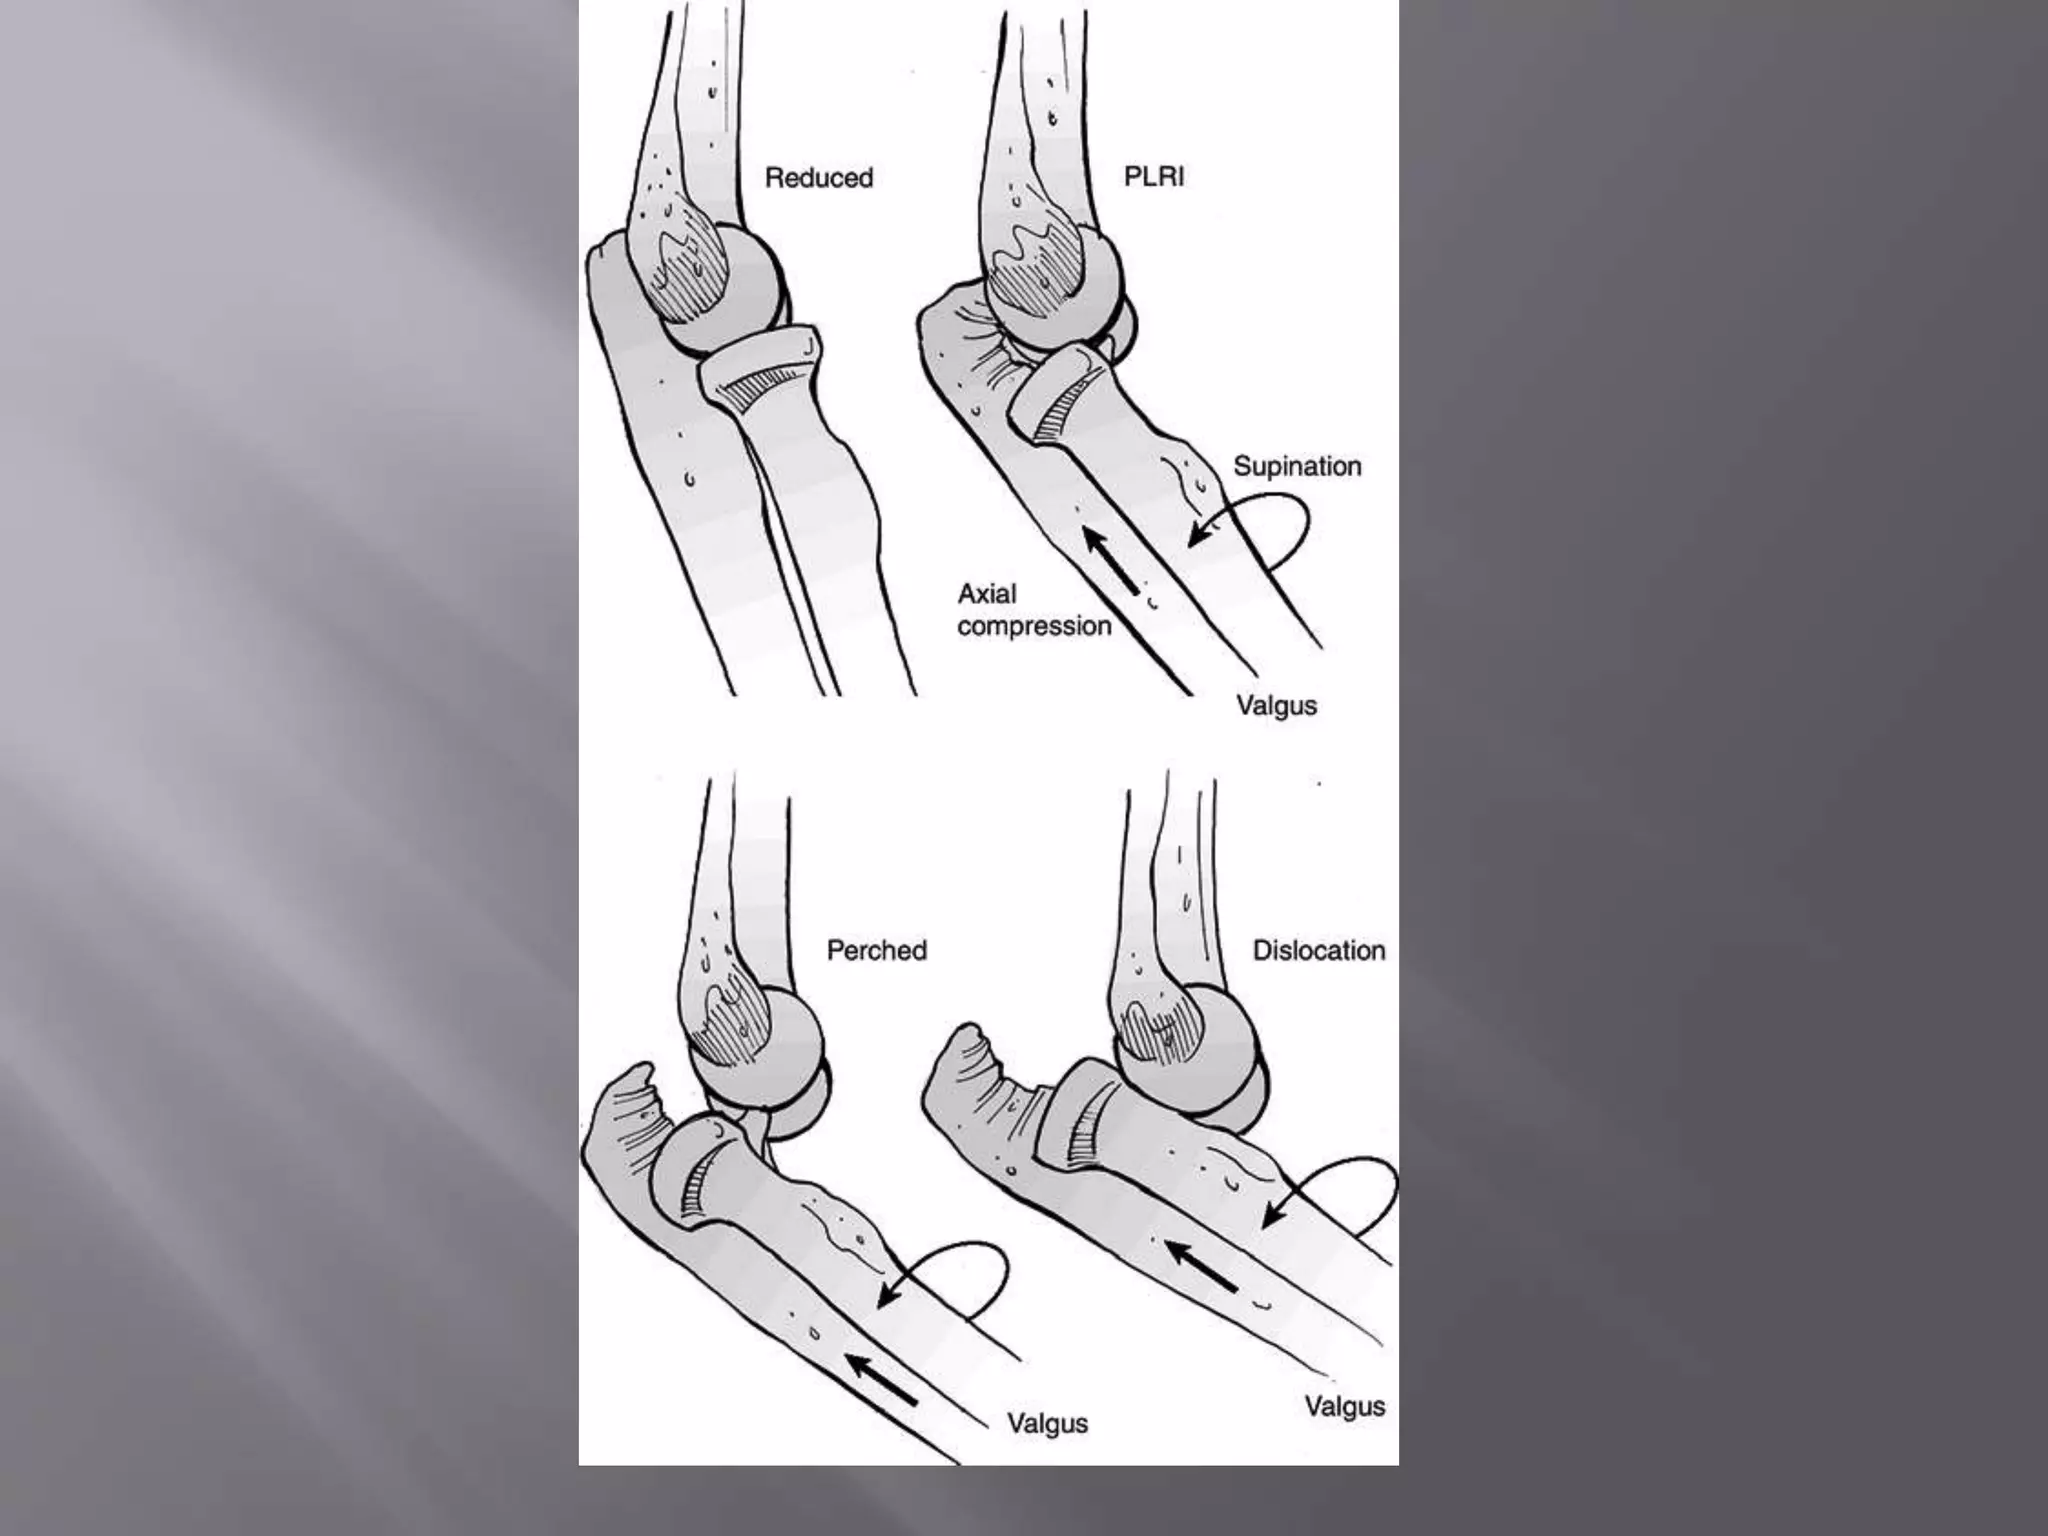

This document discusses the terrible triad injury of the elbow, which involves fractures of the radial head, coronoid process, and posterolateral dislocation. It notes the poor outcomes associated with this injury like stiffness, instability, and hardware failure. The document outlines the relevant anatomy of the medial collateral ligament and lateral uncular collateral ligament. It describes the mechanism of injury, known as the fall on an outstretched hand, and how the ligaments and capsule fail in this injury. Diagnostic imaging and classification of radial head and coronoid fractures are covered. Treatment options including observation, resection, open reduction internal fixation, and replacement are presented. Surgical approaches and techniques are also outlined.